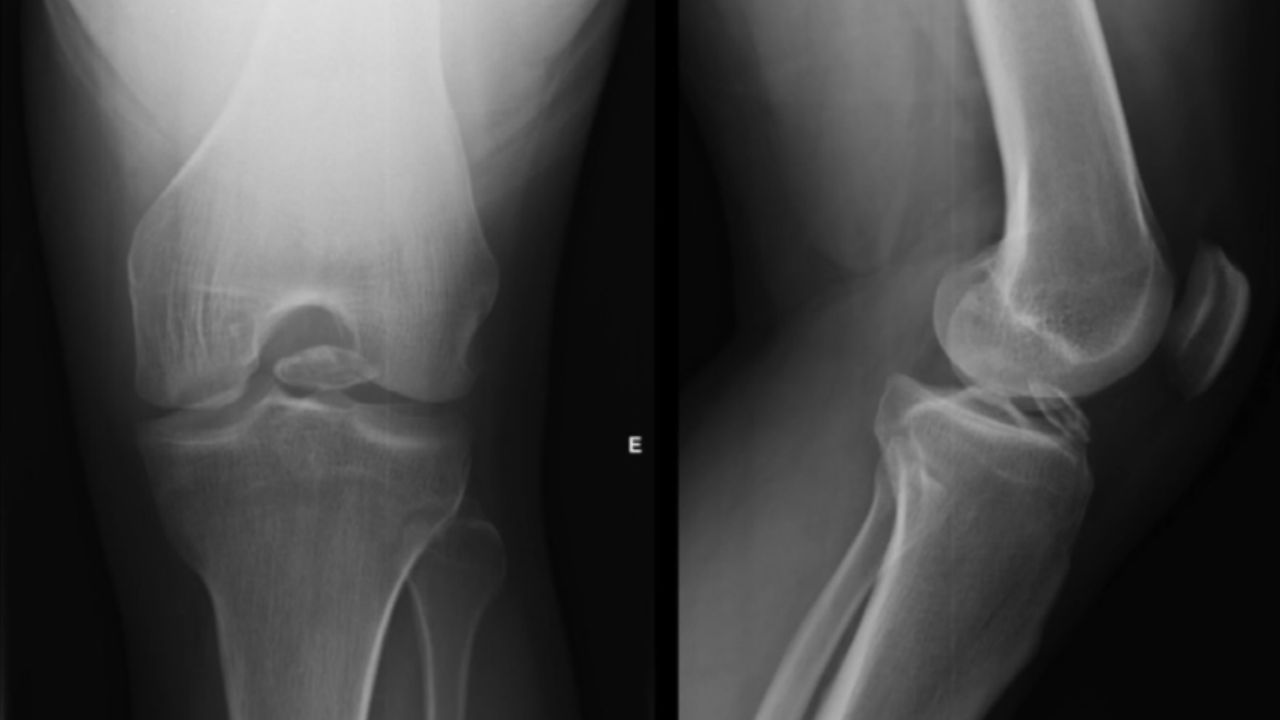

O diagnóstico é confirmado pelo ortopedista através de exames de imagem. O raio-x simples consegue identificar fragmentos ósseos, mas a ressonância magnética é o exame mais completo, pois detecta também pedaços de cartilagem (que não aparecem no raio-x) e mapeia a localização exata dos corpos livres, além de mostrar a lesão de onde eles se soltaram. Identificar a origem é crucial para tratar não apenas o sintoma, mas a causa.